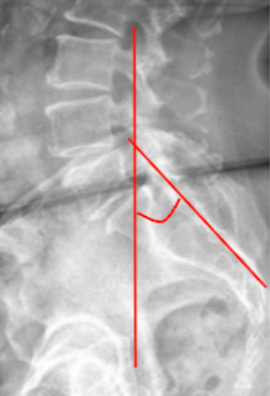

Slip Angle/Lumbosacral Kyphosis